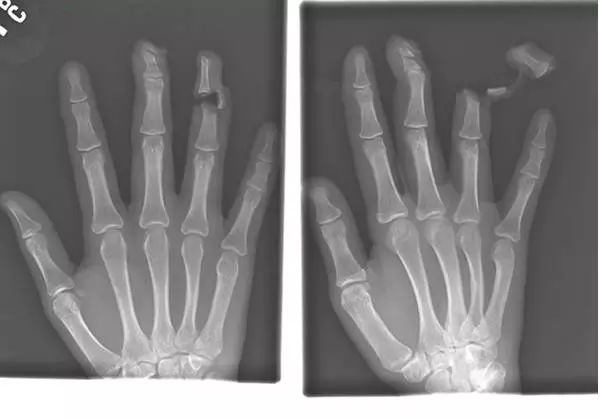

11、这名患者的X光图像显示明显的创伤,他是在与一名持刀袭击者的搏斗中受伤的: